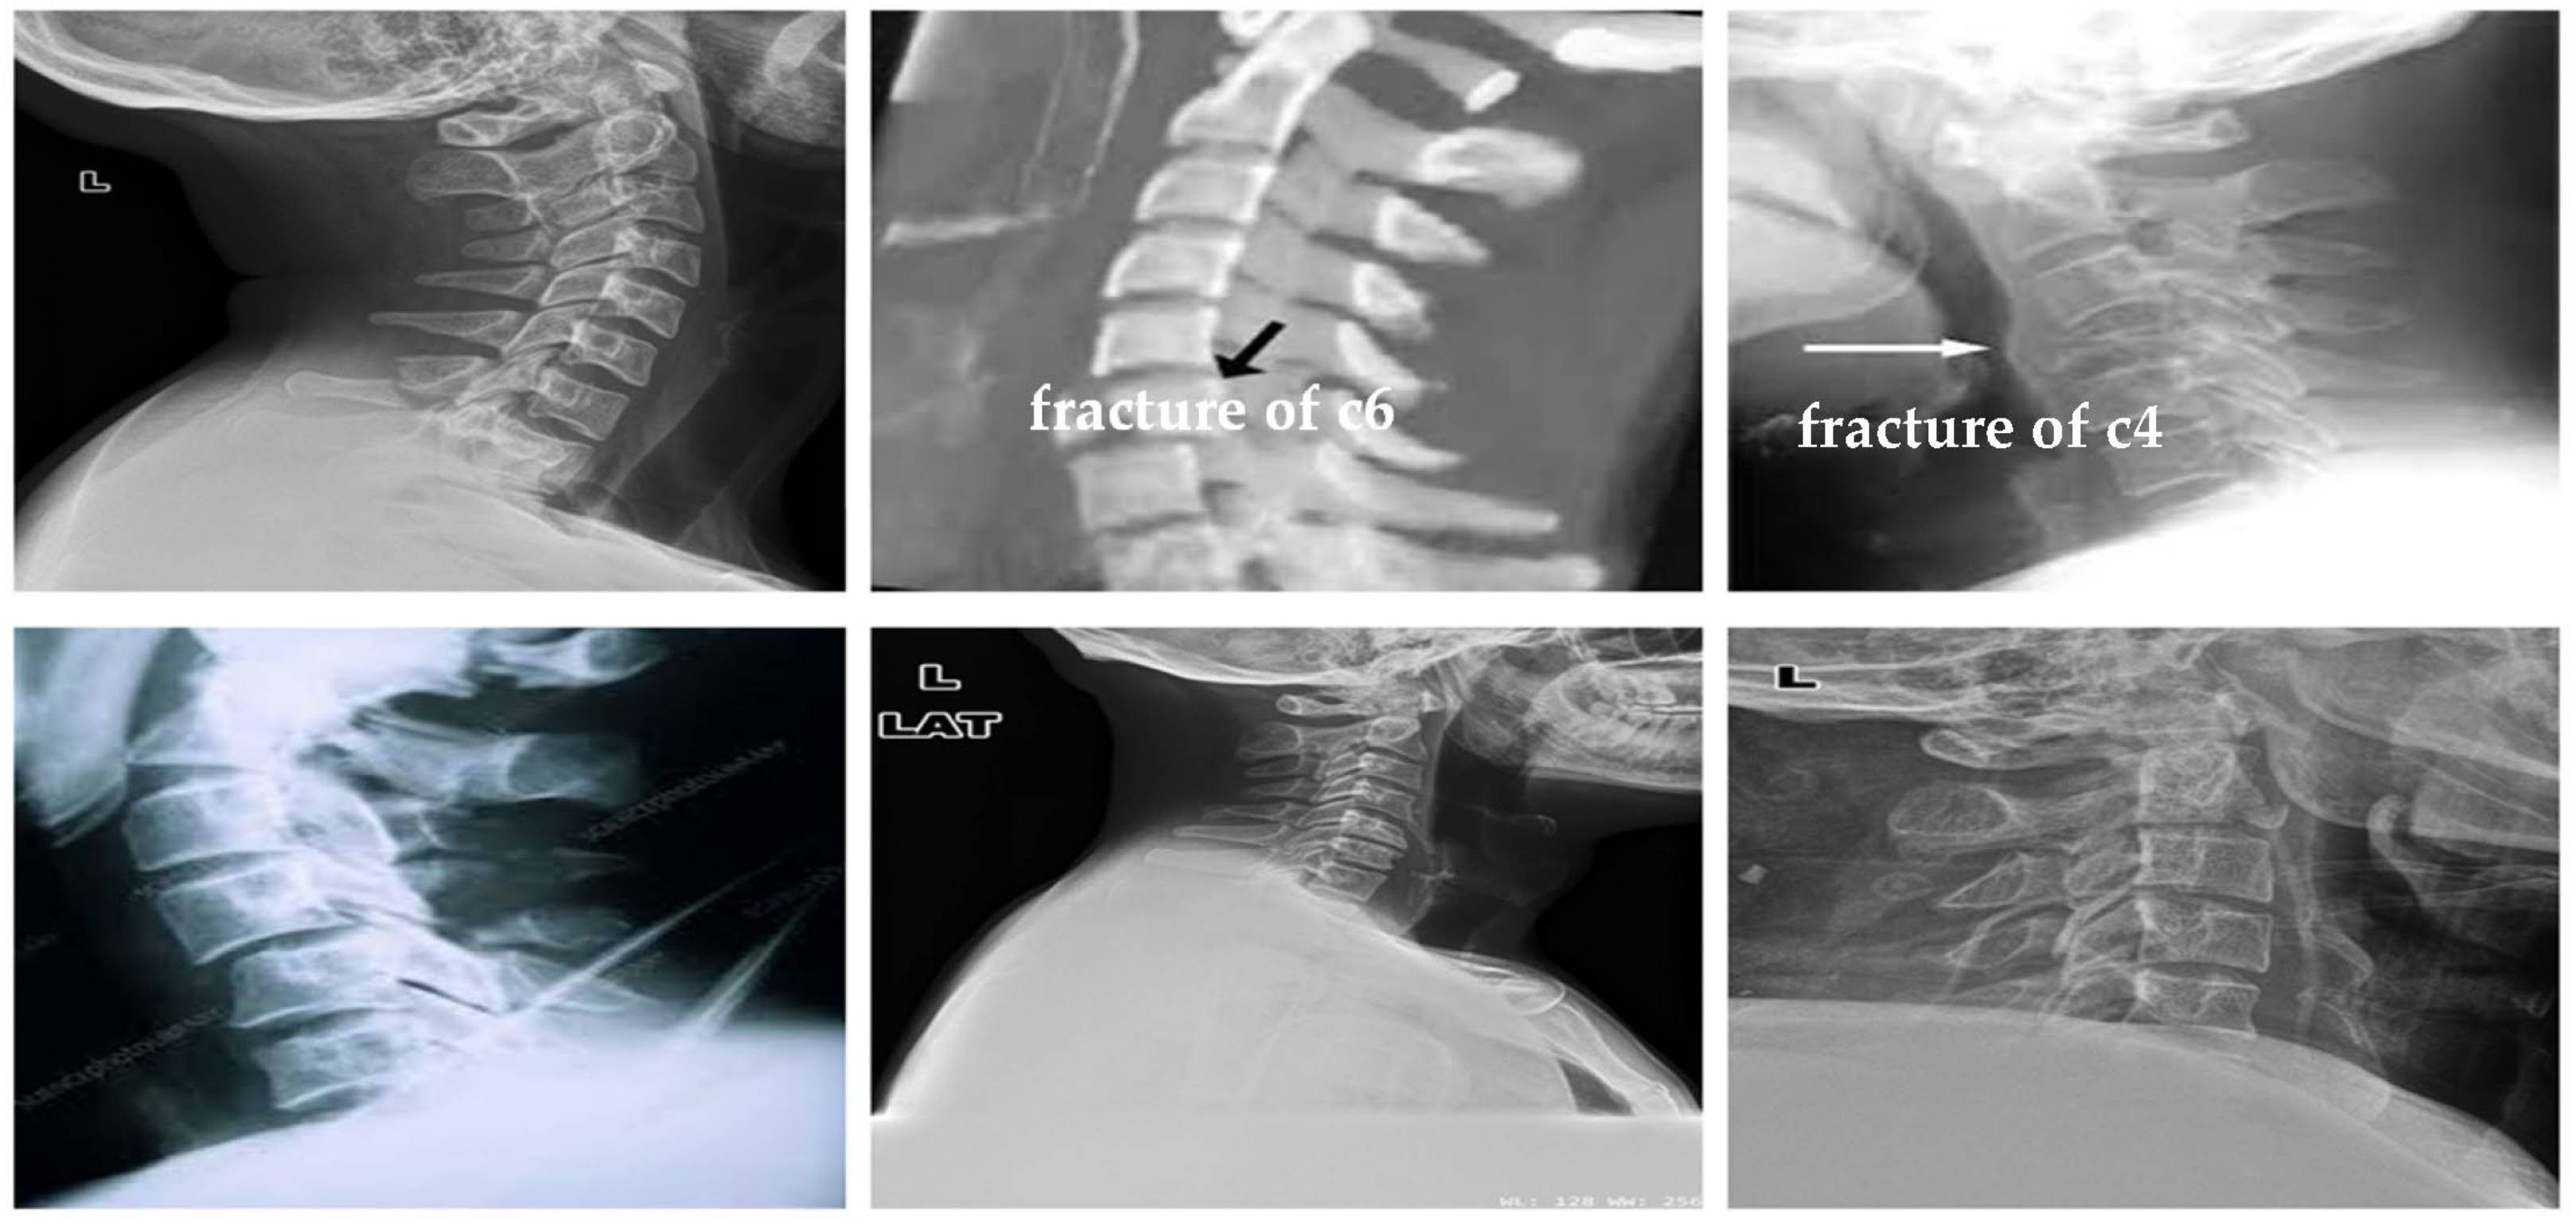

3.1. Datasets

4.1.2. Clinical Case Study